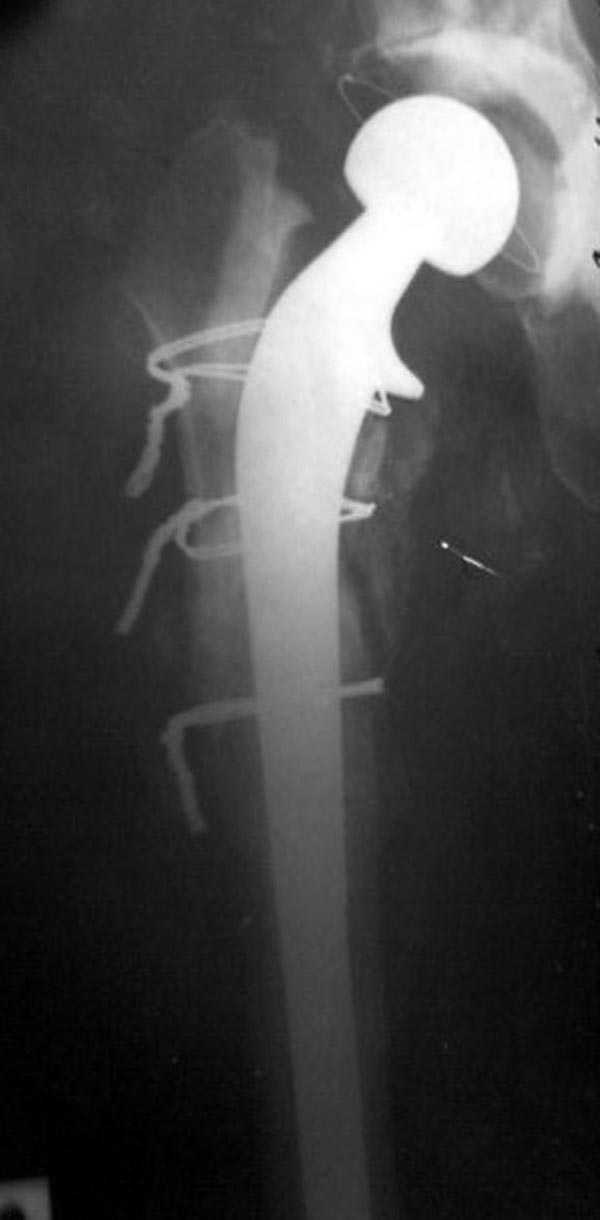

Полость вертлужной впадины и проксимальное бедро были заполнены custom made временным протезом из цемента.

Для бедренного компонента можно применить старую

длинную ножку протеза и желательно малого диаметра.

Цементная смесь наносится вручную на металл и

затем доводится до ровного диаметра поверхности

снятием лишнего цемента шаблоном. Такие шаблоны были в старом интрамедуллярном наборе, различные по диаметру отверстия на металлической пластине. Протез с цементом проводится через отверстие в шаблоне для точного совпадения с размером проксимального римера. Таким образом приготовленный феморальный компонент будет

держаться в бедренной кости плотно.

В вертлужную полость устанавливается цемент и головкой протеза выдавливается выемка, т.е. создается место для головки. В проксимальное бедро устанавливается заранее подготовленный цементный бедренный компонент.